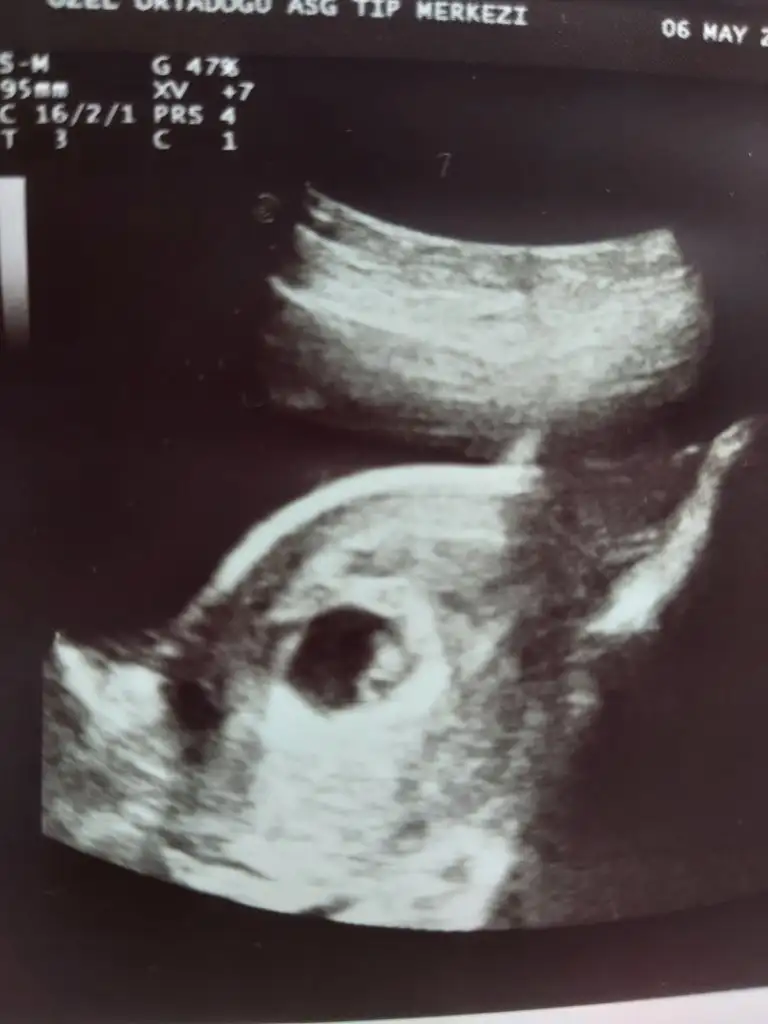

Merhabalar 10+2 haftalık hamileyim cinsiyetini çok merak ediyorum tahminde bulunursanız sevinirim teşekkürlerMerhaba millet

Ramzi teorisine göre cinsiyet tahmini yapacagim ilk ultrasyon resminizi atin bakiyim. Eger cinsiyetiniz belliyse hic söylemeeyin bakalm dogru tahmin edebilecekmiyim daha dogrusu ramzi teorisi hakli cikacak mi?

Tatlim varsa 6-7-8 haftalik usg at maalesef 10+2 ramzi teorisi icin uygun degilMerhabalar 10+2 haftalık hamileyim cinsiyetini çok merak ediyorum tahminde bulunursanız sevinirim teşekkürlerfotoğraf karından